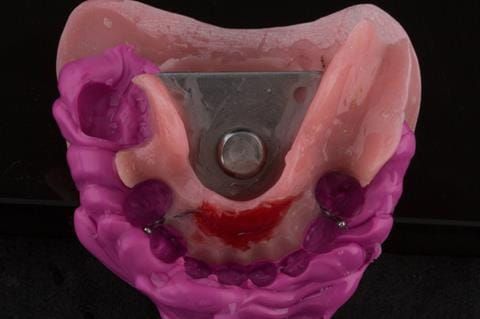

- Cobalt chromium reinforced gasket denture - using a Molloplast B "O" ring to retain and stabilise the denture. This was my professional preference as this was the least invasive and simplest solution to this dental problem. Should the UR7 require removal in the future - an artificial tooth could be added - resulting in a complete denture. The patient would have adapted to the denture fully by this stage and have good neuromuscular control of the prosthesis.

Following consultation and second discussion appointment the patient chose to have option 2 namely, a window denture - maxillary cobalt chromium based partial denture. The clinical situation and treatment process is shown in detail below with photographs. The patient was successfully rehabilitated with this and her quality of life considerably improved. The clinical work was provided by Finlay and the technical work by Rowan.